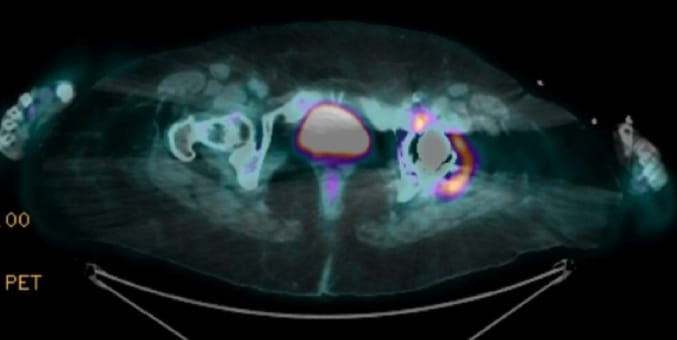

A tomografia evidenciou opacidades em vidro fosco bilaterais (Figura 1).

**Figura 1:** Imagem de tomografia computadorizada de pneumonia intersticial aguda (A), coloração com PAS de uma amostra de biópsia renal (B) e imagem obtida por microscopia eletrônica de varredura em baixo vácuo com espectrometria de energia dispersiva de raios X (C), mostrando um gráfico da concentração em massa (%) de cada elemento em um paciente exposto a fumos metálicos (e). Uma amostra de biópsia renal com glomerulonefrite membranoproliferativa foi usada como controle (d, f). A ponta da seta indica a arteríola aferente.